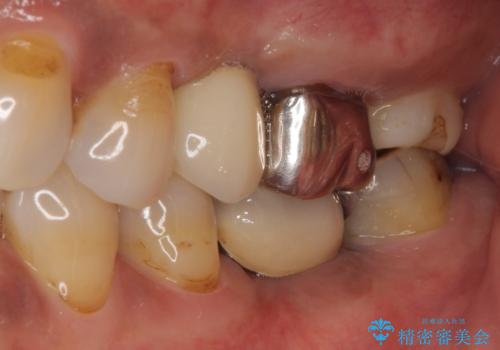

- 銀歯の装着されている奥歯がしみるとのことで来院された患者様です。

銀歯周辺の歯が欠けており、むし歯も進行している状態であったので、オールセラミッククラウンにて補綴治療を行うこととしました。